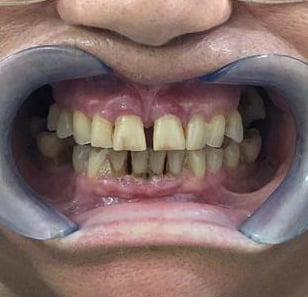

NUESTROS CASOS REALES